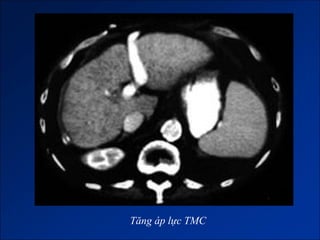

TĂNG ÁP LỰC TĨNH MẠCH CỬA

- Khí áp lực TMC >15mmHg và chênh áp cửa – chủ > 5mmHg.

- Hình thành hệ thống vòng nối cửa – chủ.

+ Vòng nối qua TM lách.

+ Vòng nối qua TM vành vị.

+ Vòng nối qua TM thực quản.

+ Vòng nối qua TM trực tràng dưới.

+ Vòng nối qua TM rốn.

Nguyên nhân

Hình ảnh trên CLVT

Tăng áp lực TMC